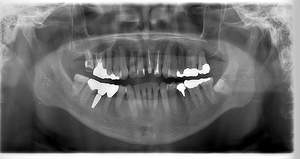

レントゲン写真

- 透過像

| 治療方針 | 右下の当該歯は歯根破折により保存不可能と診断しました。歯周疾患も伴っていたため抜歯後に骨吸収※1が大きく起こることが予測できました。チタンメッシュ併用骨再生誘導法(GBR※2)を選択しインプラント埋入と同時に行い自然な歯槽骨のラインを再現しました。またGBRを行う際にインプラント辺縁の付着歯肉の減少が起こる為、遊離歯肉移植術(FGG※3)を行い清掃性を考慮した形態に仕上げました。 ■治療方針の解説 治療した右下の歯をレントゲンで撮影したところ根本の部分に黒く写る箇所があり「根尖性慢性周囲炎※1」と診断。また歯周病も進行していました。 ※1 骨吸収・・・歯槽骨という歯を支える骨がなくなっていくこと |

| 担当者所見 | 主訴の右下だけでなく歯茎の腫れ、発赤があり不良補綴や不良充填など他にも治療箇所が多数ありました。プラークコントロールが不良であった為まずはブラッシング指導を行いセルフケアの重要性を理解していただくところからスタートしました。 右下6番の歯はインプラント治療を行なった結果審美的にも機能的にも患者様の満足を得ることができました。骨造成と歯肉移植も行なった為インプラントを支える十分な歯周組織の獲得ができたと思っております。 |